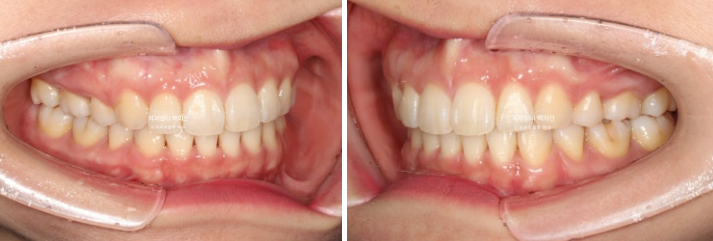

22.09~25.04